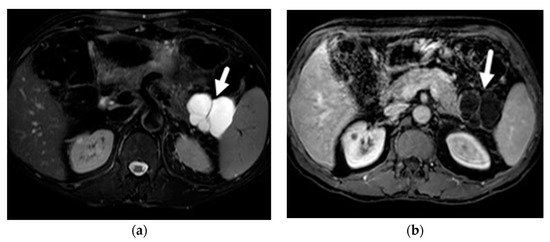

- Mamone, G.; Barresi, L.; Tropea, A.; Di Piazza, A.; Miraglia, R. MRI of mucinous pancreatic cystic lesions: A new updated morphological approach for the differential diagnosis. Updates Surg. 2020, 72, 617–637. [Google Scholar] [CrossRef] [PubMed]